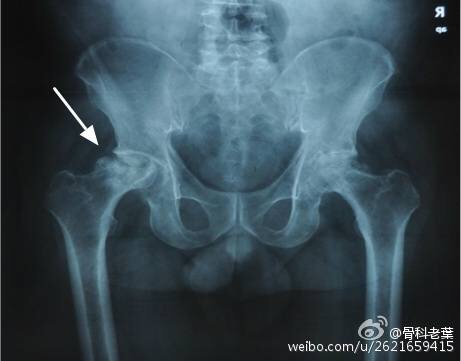

II期 病人有髋部症状,磁共振出现异常,X线片显示股骨头出现透光和硬化改变

III期 磁共振出现异常,X线片显示软骨下塌陷(新月征),股骨头内出现空洞,股骨头没有变扁

II期和III期的患者治疗方法相同,因为此时股骨头虽然还没有变形,暂时还不需要行人工关节置换术,但是股骨头已经出现空洞,随时股骨头就会塌陷变形,所以单纯的股骨头减压术是不能达到治疗效果的。这时就需要在股骨头减压的同时,植入一根支撑棒,顶住股骨头空洞区,防止股骨头在负重的情况下过早塌陷。其他治疗同之前相同,口服以上药物,定期复查,密切观察病情发展,尽量避免重体力劳动和爬山爬楼。